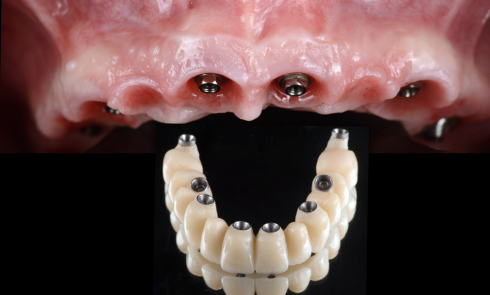

Article réservé à nos abonnés Gestion de la DVO et restaurations implantaires de grande étendue : démarche thérapeutique

Le traitement de l’édenté total constitue, de nos jours, un enjeu majeur de notre profession. Avec le vieillissement de la...